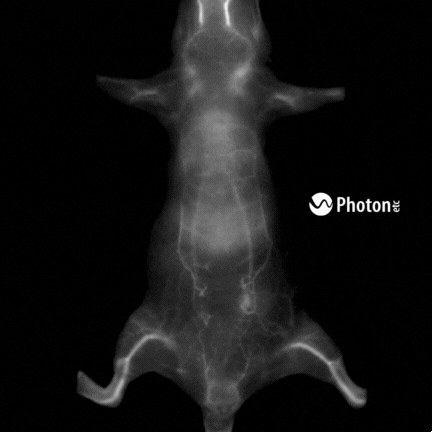

Real-Time Biodistribution of ICG in a Mouse Using NIR-II Fluorescence Imaging

Real-Time Biodistribution and Pharmacokinetics of ICG in a Mouse Using NIR-II Fluorescence

Video of IR VIVO imaging experiment showing the biodistribution and pharmacokinetics of ICG in real time. IR VIVO is able to visualize NIR probes at high resolutions. From one single injection, it was possible to obtain measurements of heartbeats, respiration and intestinal contraction rates.